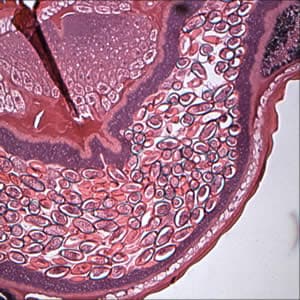

An elderly patient underwent a colonoscopy for polyps. A worm was seen near the appendiceal orifice and a biopsy was taken, fixed in formalin, and sent to histology. The sections were stained with hematoxylin and eosin (H & E). Figures A-C show what was observed on the slides at 100×, 400×, and 1000× magnification respectively. Objects such as the one shown in Figure C measured approximately 50 µm in length. What is your identification of this incidental finding? Based on what criteria?

Figure A